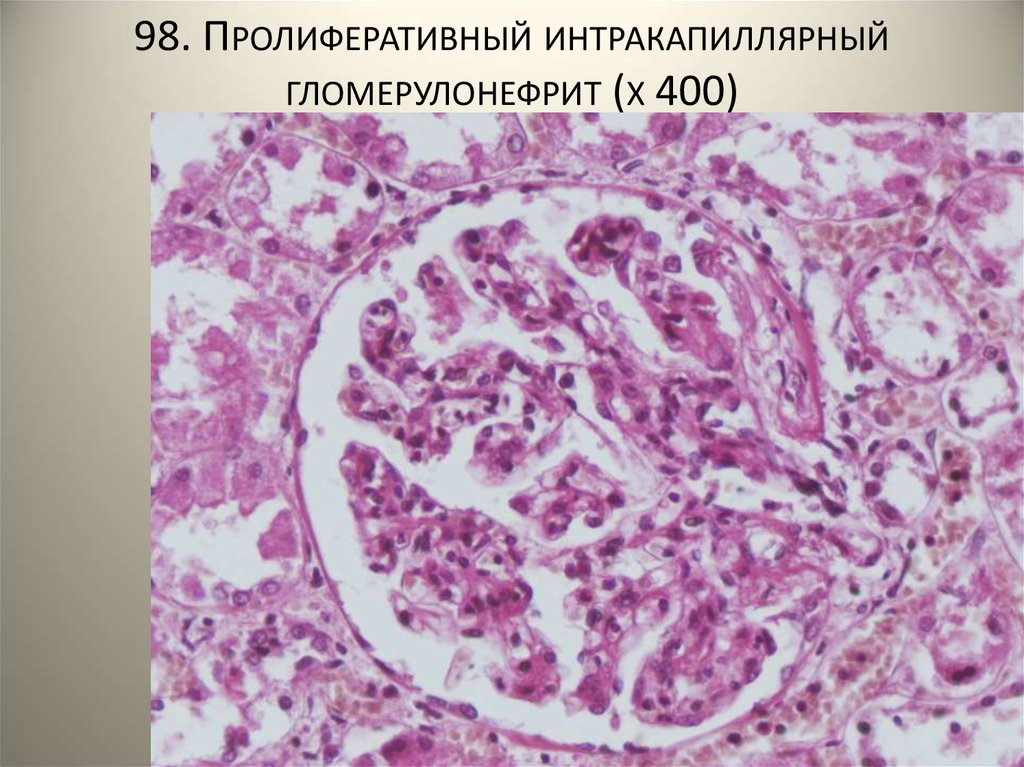

Симптомы подострого гломерулонефрита: фото и описание